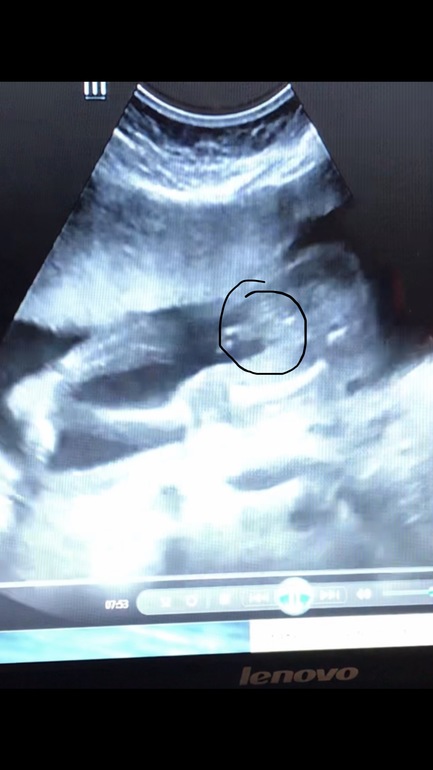

С той стороны, когда он смотрел первый раз и увидел девочку- я тоже мальчугового ничего не нашла))) Да, потом вроде увидела. Дома сто раз пересмотрела диск, сделала фотки. Ведь мальчик?НИПТ же не ошибается?